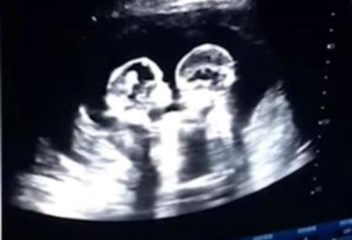

Un par de hermanas gemelas idénticas han sido vistas aparentemente peleando entre ellas mientras aún estaban en el vientre de su madre.

El video se volvió viral en China, se pudo observar a dos fetos que aparentemente se pateaban y se golpeaban mutuamente cuando su madre se sometió a una ecografía a los 4 meses de embarazo.

#Viral ¡Gemelas pelean en el vientre de su madre! En China, dieron a conocer una ecografía en la que se observa a dos bebés mantener una riña ⬇

El padre de las gemelos, Tao, de 28 años, dijo que las imágenes fueron filmadas por él cuando acompañó a su esposa a un control prenatal a fines del año pasado en la ciudad de Yinchuan.